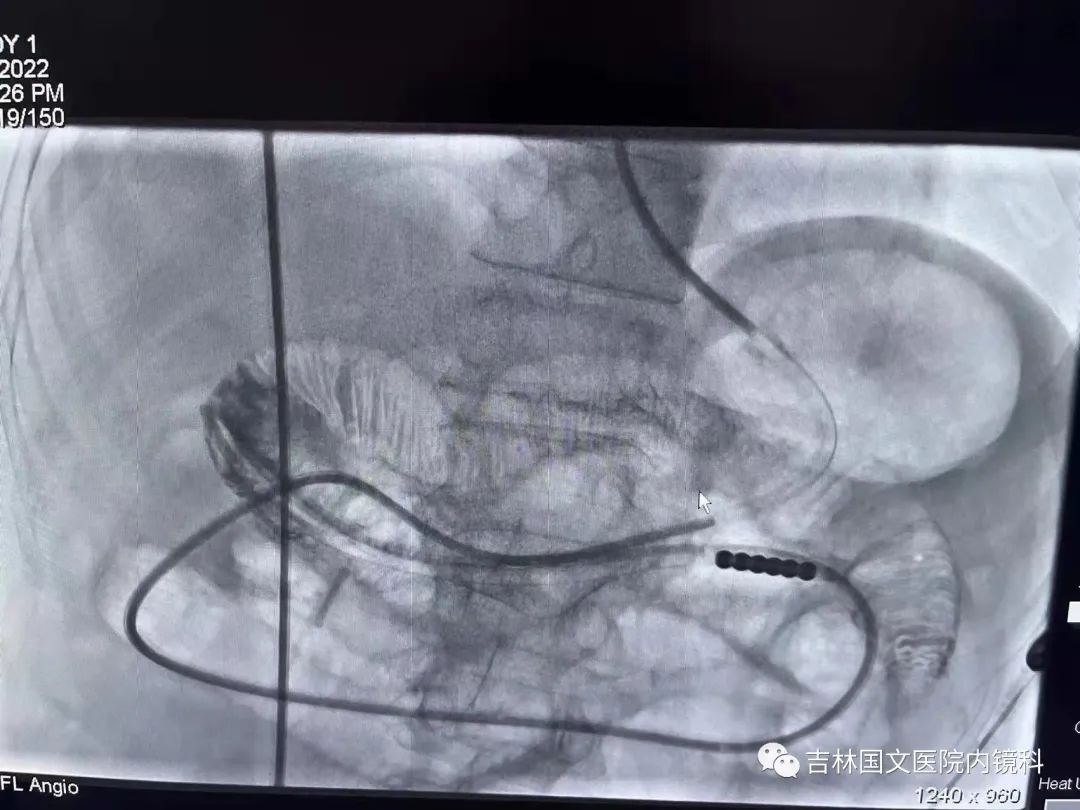

這是一位胃術(shù)后的患者,也就是說胃內(nèi)許多正常的解剖結(jié)構(gòu)都已經(jīng)切除,這就會造成腸梗阻導(dǎo)管易迷失方向,猜測哪邊才是真正的出口是這次操作成功的關(guān)鍵,這就需要我們的“第三只眼”--胃鏡,胃鏡再加上邢主任豐富的經(jīng)驗,在一個又一個岔路口為腸梗阻導(dǎo)管引路,判斷方向,遇山開荒,遇水搭橋,即使崎嶇,只要不放棄,終將成功。